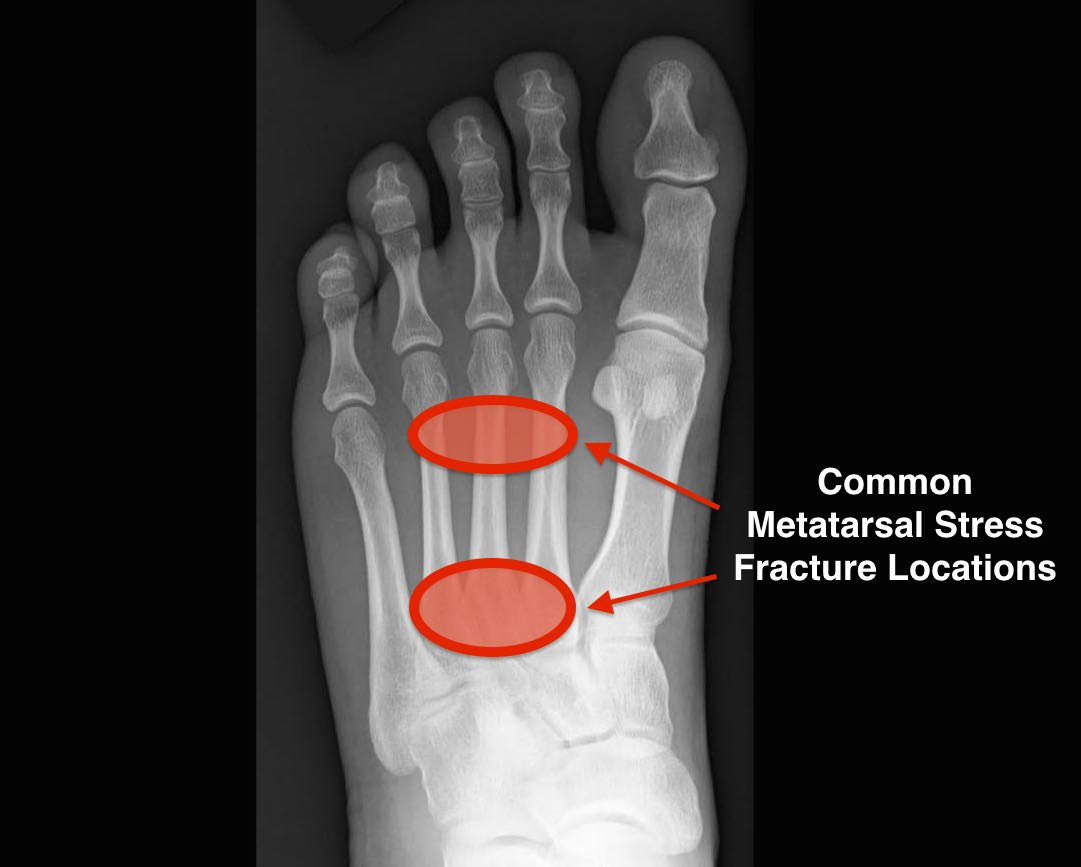

Stress fractures can have multiple symptoms, ranging from a dull ache in the middle of the foot to a sharp pain while standing and walking. Stress fractures can occur in many places along the metatarsal length, and can sometimes occur in several bones as once.